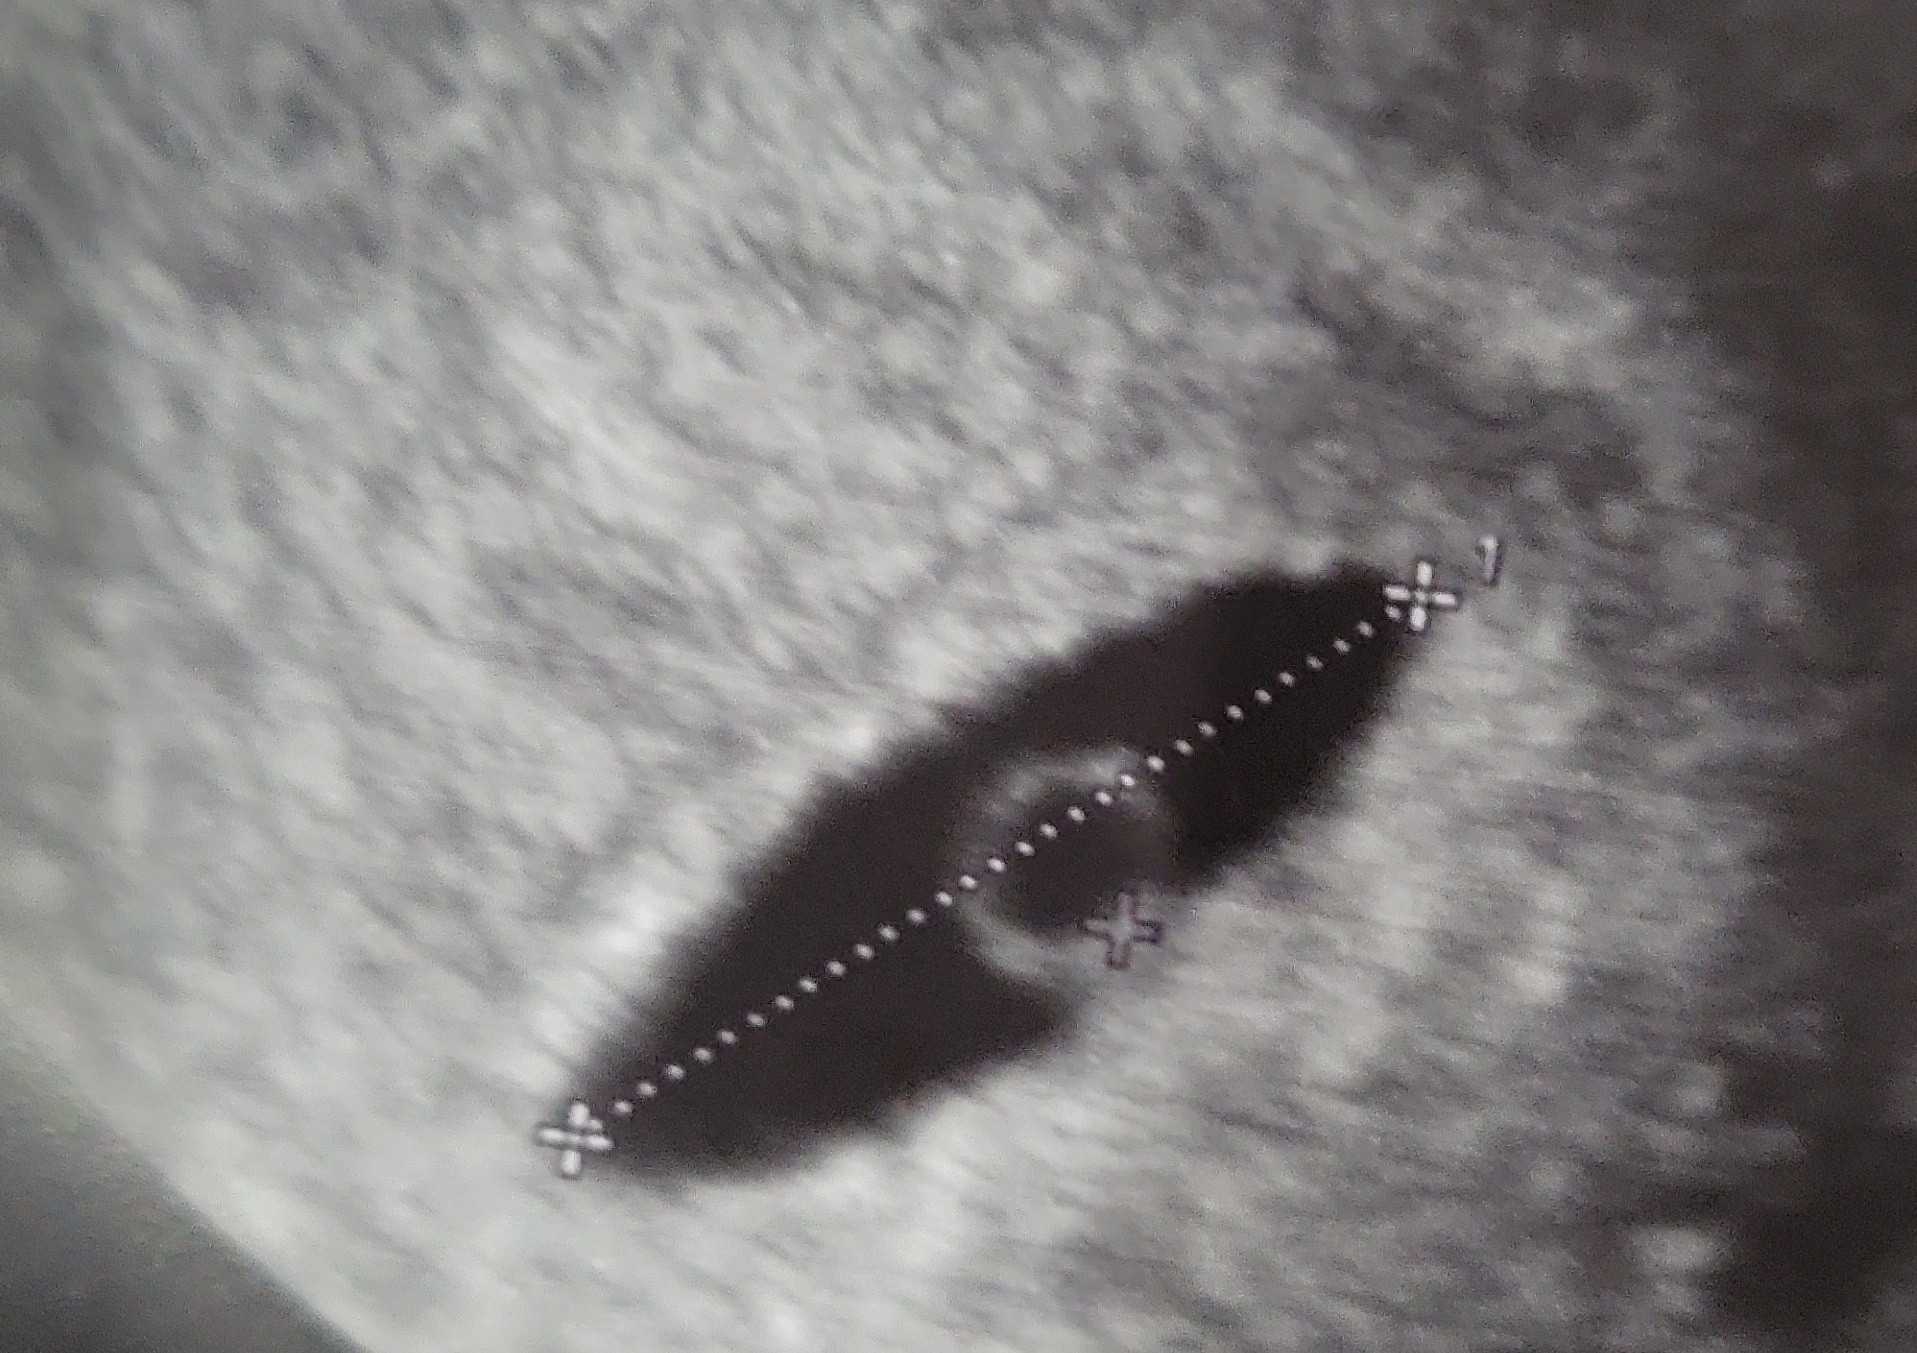

Dnia 7.11 było moje 1 usg dokładnie 4w5d i mały pecherzyk ciazowy 3mm

Dnia 15.11 (5w6d)- Zmienilam lekarza-moje drugie usg spowodowane jakaś dziwna infekcja, a oto efekt. Coś nie coś widoczne. Jednak martwi mnie wielkosc pecherzyka - aż 14,5 mm. Martwi mnie to że jest taki plaski... Lekarz nic nie mówił oprócz obdarowania mnie prolutexem.

Co myślicie? Czy to już paranoja?

Zobacz załącznik 1465817